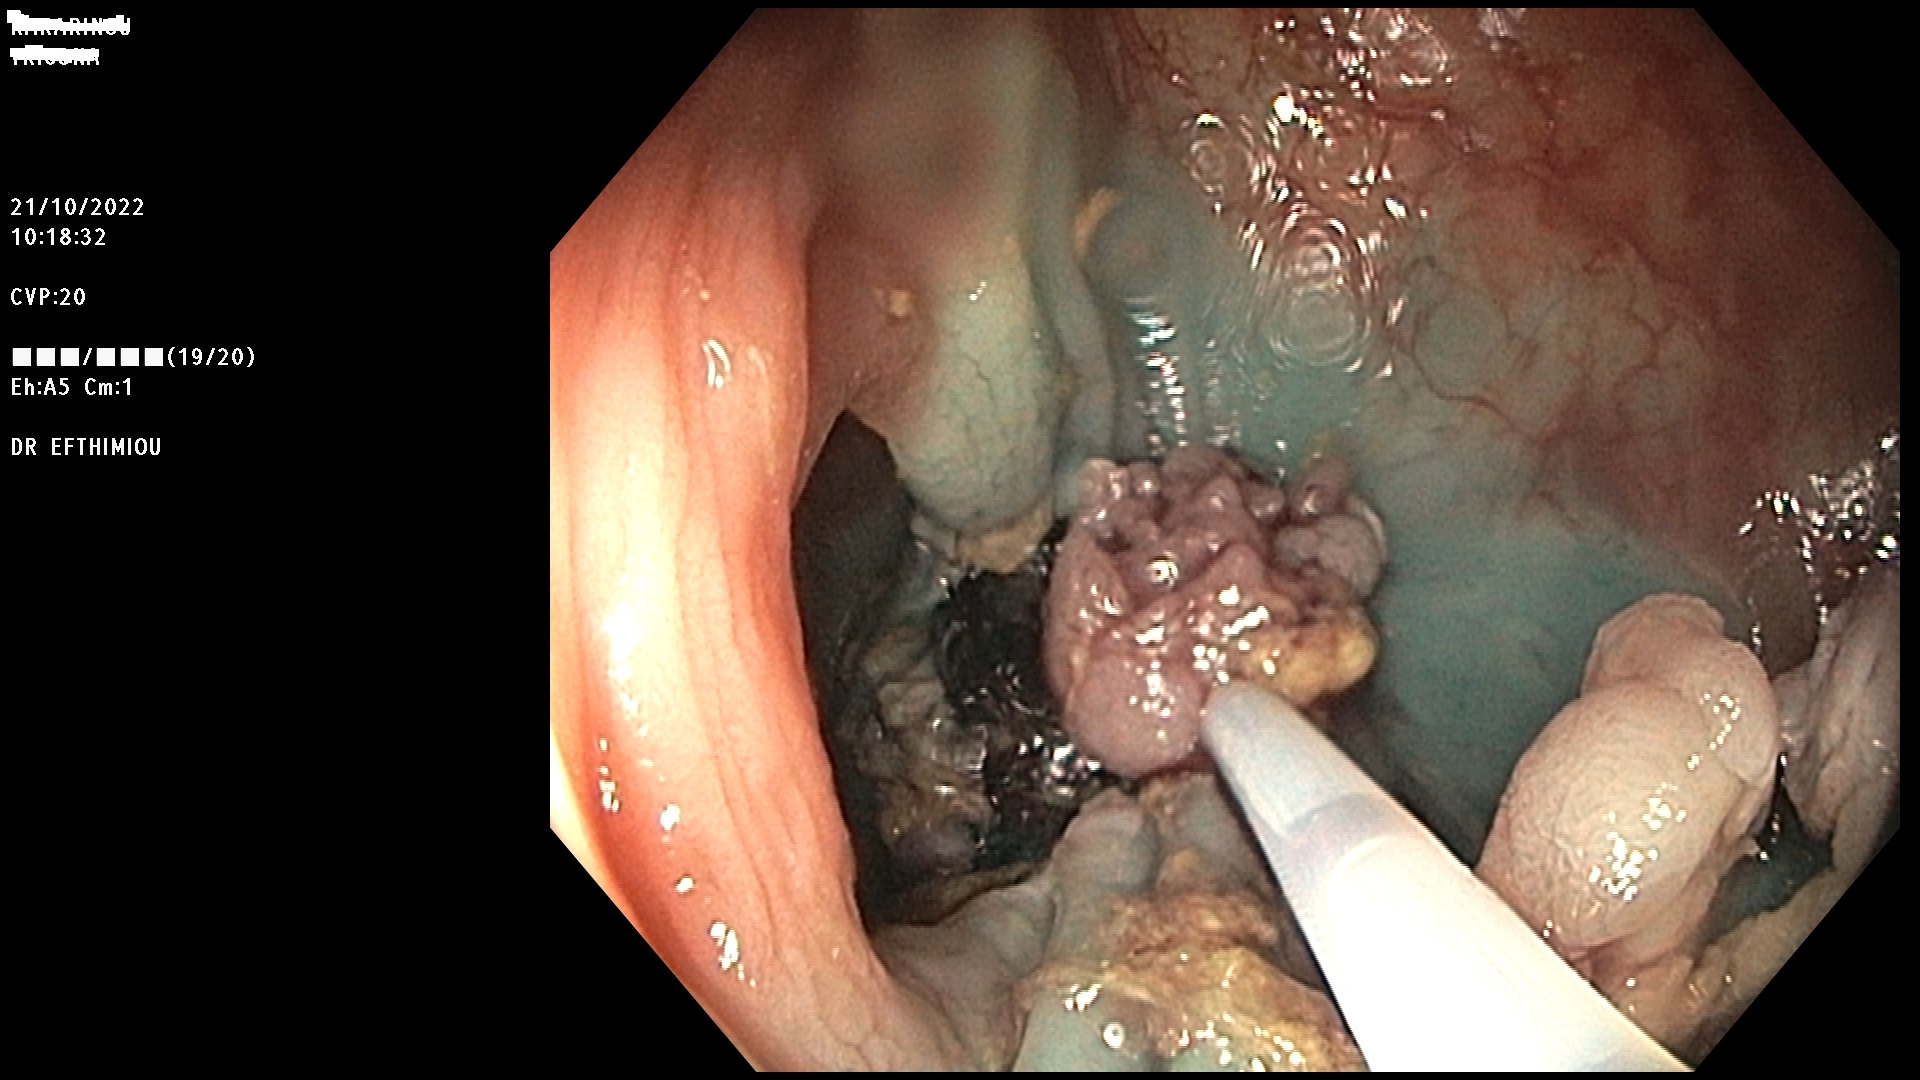

Η επέμβαση γίνεται κατά τη διάρκεια της κολονοσκόπησης με τη χρήση

διαφόρων εργαλείων (λαβίδες, βελόνες υποβλεννογόνιας έγχυσης, βρόχοι

διαθερμίας, ψυχροί βρόχοι, endoloops, κ.ά.) ανάλογα με το μέγεθος, τη

μορφολογία και την εντόπιση του πολύποδα (Εικόνες 1-3). Ο ασθενής

βρίσκεται σε ήπια καταστολή («μέθη») και δεν αισθάνεται καθόλου πόνο.